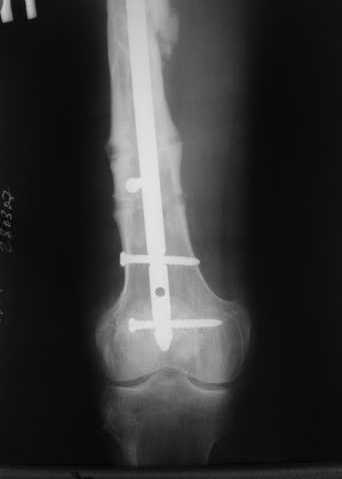

27 марта выполнено удаление блокирующих винтов (сломанный винт пришлось высверливать цапфен-бором), сломанного штифта (дистальный фрагмент удален через канал, образованный разверткой из коленного сустава - image 4),

рассверливание костно-мозгового канала, реостеосинтез штифтом UFN (при проведении штифта в дистальном отломке мы использовали поляризующий винт, диаметр штифта 10 мм). После операции в связи гемартрозом дважды (на 1 и 3 сутки) выполняли пункцию коленного сустава. Сейчас признаков скопления жидкости в полости сустава нет. Послеоперационные рентгенограммы - images 5, 6, 7.